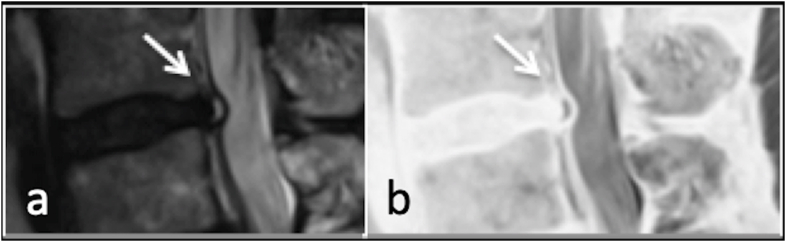

Fig. 2.

T2 sagittal (a) and inversion (b) showing annular fissure (arrow).